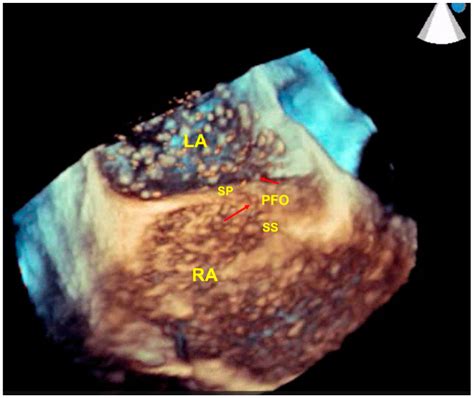

Case 1: 2D-and 3D-TEE images after transcathete…

466×466

researchgate.net

Case 1: Volumetric and multiplanar 3D-TEE image…